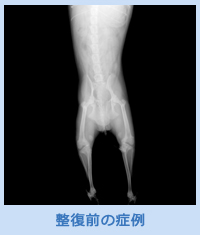

小型犬のトイ種では、ソファーやベッドからの転落や落下による骨折が生じることが多くあります。骨折した犬は足を挙上し、使わなくなります。そのため、速やかに診断し、治療が必要です。レントゲン検査を行うことで、どのような骨折が生じているのかを正確に把握し、骨の整復にはどのようなアプローチを行うべきかを判断します。

このような症例に対しては骨髄内へのピンの挿入やプレートを設置することで骨の整復を行います。ピンやプレートのサイズはレントゲンを基にして適切な厚さは大きさを選択します。(下部写真参考)